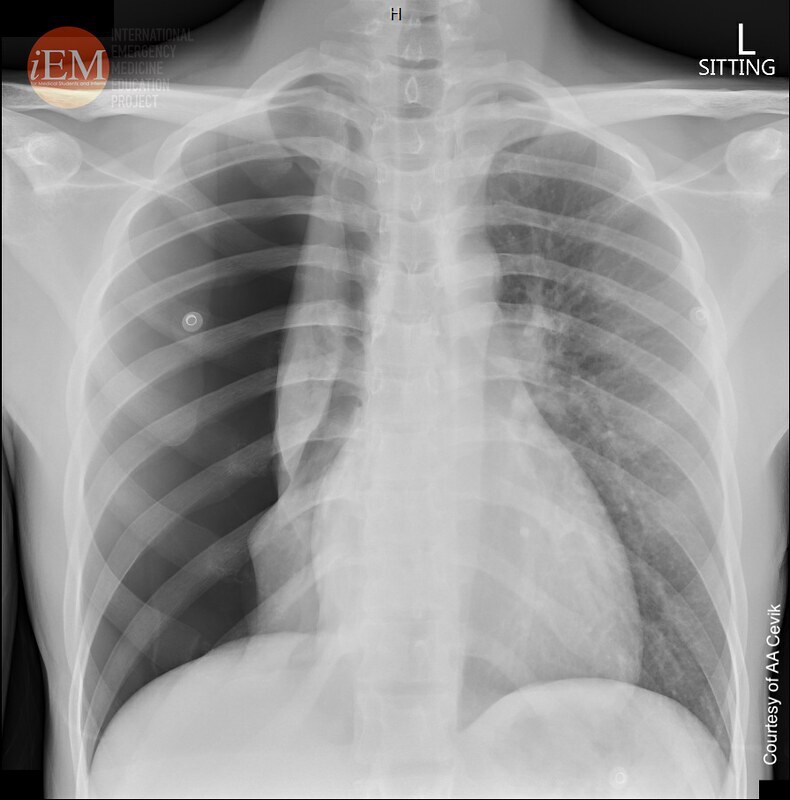

13

Q

what does this CXR show?

A

simple pneumothorax

- visible rim of air between lung margin + chest wall

- no visible lung markings